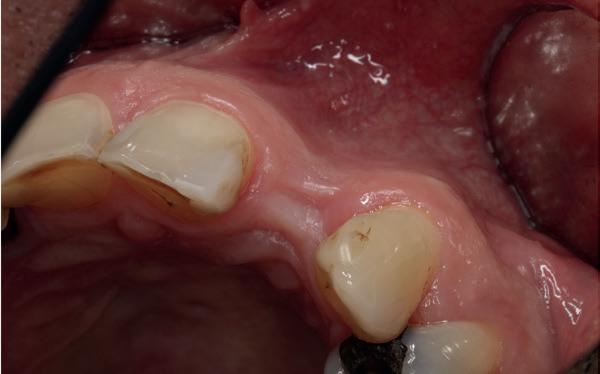

Een gezonde, jonge dame had op 8-jarige leeftijd een trauma op school waarbij ze op haar voortanden was gevallen. Volgens haar moeder waren deze voortanden tot onder het tandvlees afgebroken. Nadat ze

via de spoeddienst bij de kaakchirurg terechtkwam, werd daar besloten tot extractie van de 11 en 21. In de opinie van de auteur is dit een te voorbarige behandeling geweest; de kans dat beide centrale incisieven bij een meisje van 8 jaar na een val zodanig beschadigd zijn dat de radices zonder kans op behoud verwijderd moesten worden, is bijzonder klein. Helaas was het kwaad al geschied.

Op 16-jarige leeftijd werd de patiënt door haar behandelend orthodontist naar de auteur verwezen voor een restauratieve oplossing voor de afwezige 11 en 21. In de tussenliggende periode had patiënt een retainer gedragen met twee kunststof tanden (afbeelding 1). Zowel de patiënt als haar moeder hadden een sterke voorkeur voor een implantaat gedragen vaste oplossing. Gezien haar jonge leeftijd was dit echter nog geen optie, omdat er nog verticale groei te verwachten viel. Implanteren op jonge leeftijd – dat wil zeggen vóór het 21e levensjaar – kan resulteren in een infrapositie van het implantaat, omdat de rest van het gebit nog verticaal kan doorgroeien.

Middels shared decision making werd het volgende plan overeengekomen: eerst zou er een etsbrug met vleugels op de 12 en 22 worden vervaardigd, om op 21-jarige leeftijd verder te gaan met implantologie.

Bij klinisch en röntgenologisch onderzoek viel echter op dat radix van de 12 en 22 een convergerende (de radices staan dan naar mesiaal en naar elkaar toe) in plaats van divergerende (radices staan dan van elkaar af) stand had. Door deze convergerende stand van de radices was er in mesio-distale zin geen ruimte voor twee implantaten ter plaatse van de 11 en 21. Er werd daarom besloten, in tegenzin

1. Retainer met twee frontelementen

2. OPT radices 12 en 22 convergeren

3. Vaste apparatuur voor torque 12 en 22

4. OPT radices 12 en 22 divergeren na orthodontische behandeling

van de patiënt, om eerst weer vaste apparatuur terug te plaatsen om de radices in een divergerende stand te plaatsen. Gelukkig verliep deze behandeling voorspoedig. (afbeelding 2 -4). Het volgende behandelplan werd gemaakt:

• Intra-orale scan voor studiemodellen, proefopstelling en beoordelen ruimte palatinaal

Vervaardigen essix retainer met dummies waarbij er een emergence profile van de 11 en 21 werd gevormd door eivormige dummies 4 mm in de gingiva te plaatsen

• Aanvulling zachte weefsels met de VISTA techniek en een vrij gingivatransplantaat uit het palatum links en direct dragen van de essix retainer

Na 4 weken intra-orale scan voor de etsbrug en kleurbepaling bij de technicus

• Plaatsen van de etsbrug met een composietcement

Voordat er gescand kon worden voor een etsbrug, werd een studiemodel vervaardigd om met de technicus te overleggen of er voldoende ruimte was voor 2 centrale incisieven in de mesio-distale zin en of er voldoende ruimte was in occlusie voor de vleugels van de etsbrug. Er hoeft enkel nog aan de 12 en 22 pala-

tinaal geslepen te worden als er geen 1,5 mm ruimte voor de vleugels behaald kan worden. De ruimte was op de dunste plekken 1 mm, dus een kleine preparatie in de 12 en 22 palatinaal was nodig. Omdat de kaak volledig afgevlakt was en dun was geworden, kunnen de dummies van de etsbrug enkel op de kaak “gelegd worden”, maar daarbij zijn er geen papillen en staat de cervicale rand van de dummies net voor de kaak. Een esthetisch resultaat kan daarmee niet behaald worden. Daarom is een aanvulling van de zachte weefsels in de breedte nodig, als het creëren van een emergence profile, waarbij het oogst alsof de gebitselementen uit het weefsel vertrekken.

5. Beginsituatie voor behandeling